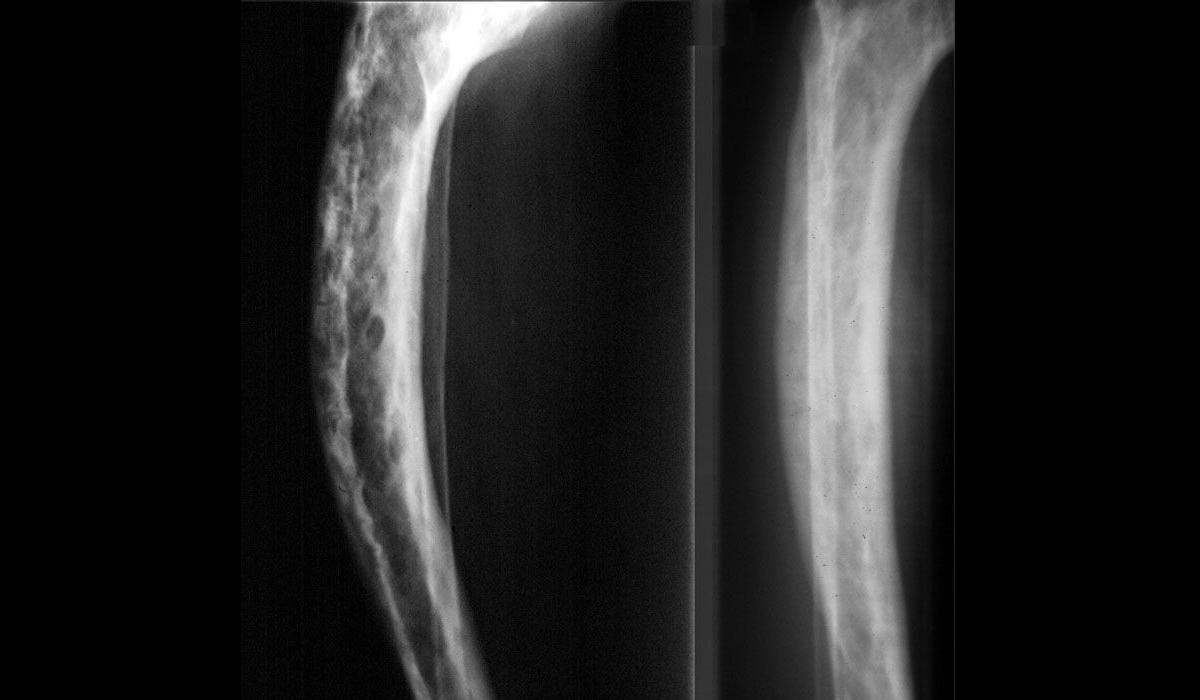

Paget hastalığı ‘’Osteitis deformans‘’ olarak da bilinen iyi huylu kronik kemik hastalıklarından birisidir. İleri yaşlarda grubuna osteoporoz yani kemik erimesi hastalığından sonra en sık görülen kemik rahatsızlıklarından bir tanesidir. Bu hastalığın en belirgin özelliği hastalığın aşırı miktarda kemik yıkımına sebep olmaktadır. Genellikle 50 yaş üzerinde görüldüğü bilinmektedir.

Bu hastalığın bilinen ilk belirtisi kemik ağrısıdır. Fakat dikkat edilmesi gereken konu her kemik ağrısı paget hastalığını temsil etmez. Kemik ağrıları sonrasında  travmalar ve meydana gelen kırıklık ve kırıkların geç iyileşmesi ise hastalığın bilinen belirtileri arasındadır. Paget hastalığı bulunduğu alan ve etkilenen kemiğe göre farklı belirtiler ortaya çıkabilir.